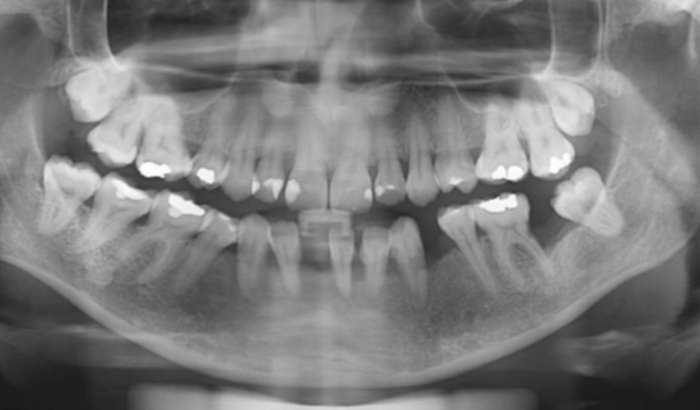

Eu sou a Jéssica, criei essa vaquinha para ajudar no meu tratamento dentário, pois sou diabética (mody3) e devido a essa doença desenvolveu uma doença grave na minha boca e estou perdendo os dentes da boca.